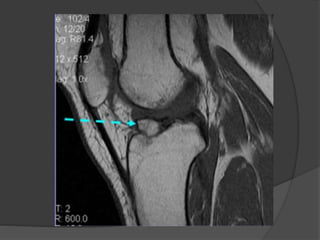

Fracturas osteocondrales

Osteocondritis disecante

 lesión osteocondral originada por traumatismo (50%)

 Mas frecuente niños y adolescentes, en los que el cartílago

articular es más resistente que el hueso subcondral.